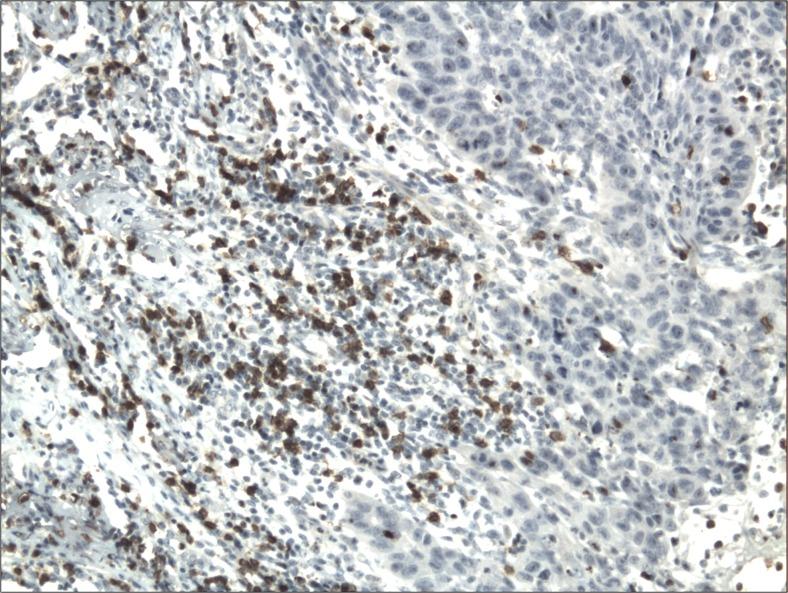

口腔鳞状细胞癌中Foxp3、CD4、CD8细胞浸润及程序性死亡受体配体1的免疫组织化学分析

Immunohistochemical Analysis of Foxp3, CD4, CD8 Cell Infiltrates and PD-L1 in Oral Squamous Cell Carcinoma.

The immunoexpression of the PD-L1 and the number of immune infiltrating cells have been shown to be a significant prognostic factors in various human cancers. Immunohistochemical method was used to examine the immunoexpression of PD-L1 and number of Foxp3+, CD4+, CD8+ cells in 78 cases of oral squamous cell carcinomas (OSCCs): with better prognosis - OSCCBP (n = 37), and with poorer prognosis - OSCCPP (n = 41), and 18 cases of normal mucosa as a control. The immunoexpression of PD-L1 and the mean number of Foxp3+ cells was significantly increased in OSCCPP group in comparison to OSCCBP and control groups. The mean number of CD4+ cells was significantly increased in OSCCPP group in comparison to OSCCBP and control groups. CD8+ cells were significantly more numerous in OSCCBP group in comparison to OSCCPP and control group. In both OSCCPP and OSCCBP groups there were positive significant correlations between number of Foxp3+ and CD4+ cells. We found positive correlations between the immunoexpression of PD-L1 and numbers of Foxp3+ cells, and negative correlation between the immunoexpression of PD-L1 and numbers of CD8+ cells in both OSCCPP and OSCCBP groups. We found also significant positive correlation between immunoexpression of PD-L1 and the number of CD4+ cells in OSCCPP group. In conclusion, our findings support the hypothesis of involvement of Tregs and PD-L1 in OSCC development and progression.

PD-L1的免疫表达和免疫浸润细胞数量已被证明是多种人类癌症的重要预后因素。采用免疫组织化学方法检测78例口腔鳞状细胞癌(OSCC)中PD-L1的免疫表达以及Foxp3+、CD4+、CD8+细胞的数量:预后较好的OSCCBP组(n = 37),预后较差的OSCCPP组(n = 41),并以18例正常黏膜作为对照。与OSCCBP组和对照组相比,OSCCPP组中PD-L1的免疫表达和Foxp3+细胞的平均数量显著增加。与OSCCBP组和对照组相比,OSCCPP组中CD4+细胞的平均数量显著增加。与OSCCPP组和对照组相比,OSCCBP组中CD8+细胞数量明显更多。在OSCCPP组和OSCCBP组中,Foxp3+细胞数量与CD4+细胞数量之间均存在显著正相关。我们发现,在OSCCPP组和OSCCBP组中,PD-L1的免疫表达与Foxp3+细胞数量之间呈正相关,而PD-L1的免疫表达与CD8+细胞数量之间呈负相关。我们还发现,OSCCPP组中PD-L1的免疫表达与CD4+细胞数量之间存在显著正相关。总之,我们的研究结果支持Tregs和PD-L1参与OSCC发生发展的假说。